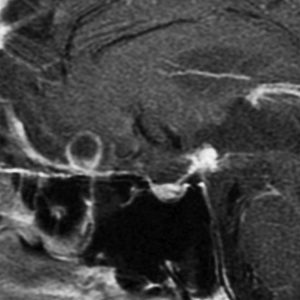

とにかく失明を避けるために急いで経蝶形骨洞手術(transsphenoidal-transtuberculum sellae approach)で腫瘍のう胞の減圧をしました(緑の矢印の経路 by 函館中央病院加藤功先生)。その後に前頭開頭で腫瘍を全摘出しました(右側の画像)。尿崩症はでましたが下垂体前葉機能は正常です。

右視力 0.45,左明暗弁の視力が残りました。でももし,経鼻手術をしないでいきなり開頭すればおそらく全盲になっていた例です。